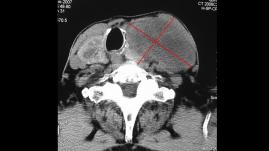

• Papiller tiroid kanserinin az diferansiye kansere dönüşümü

Papiller tiroid kanserinin az diferansiye kansere dönüşümü